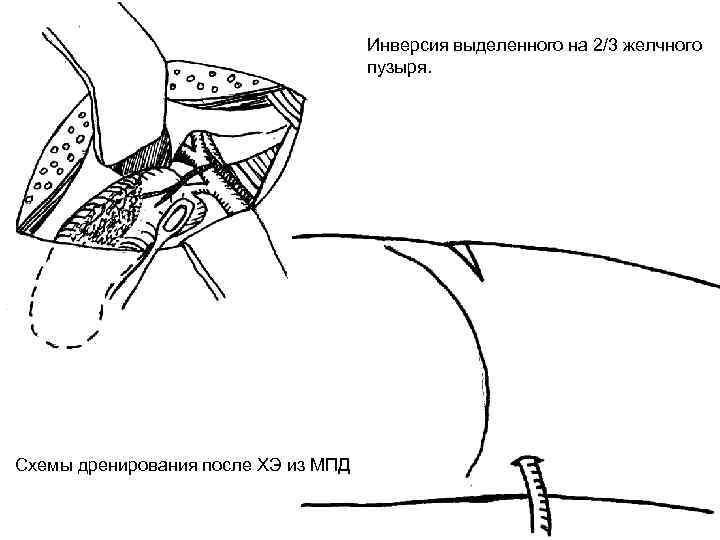

Кіші жолмен жасалатын холецистоэктомия Көрсеткіштері: - жедел калькулезді холецистит - холецистолитиаз, холедохолитиаз, кеңеймеген; -ЛХЭ кезіндегі техникалық қиыншылықтар. Қарсы көрсеткіштер: - іш қуысы ағзаларын интраоперационды ревизия жасау қажеттілігі; - Жайылған перитонит.

Вскрытие брюшины при ХЭ из МПД. Захват дна желчного пузыря окончатым зажимом. Субсерозное выделение желчного пузыря с помощью электрокоагуляции.

Инверсия выделенного на 2/3 желчного пузыря. Схемы дренирования после ХЭ из МПД